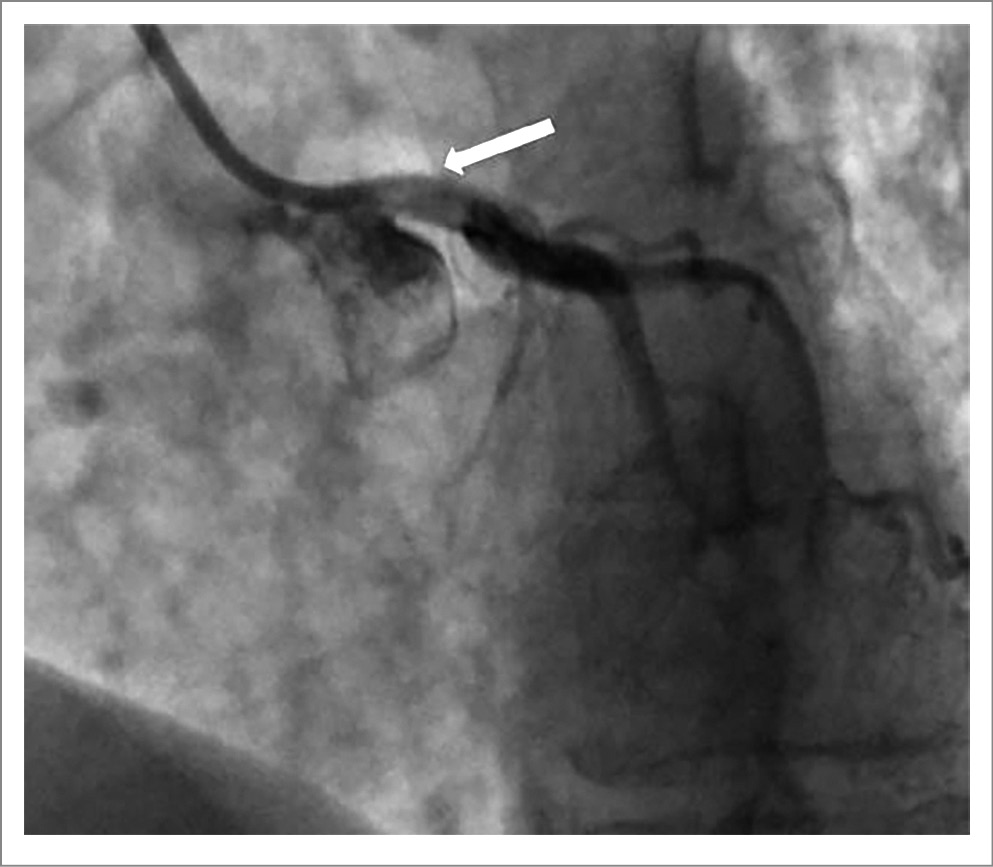

28.05.2020 проведено МСКТ-исследование легких с ангиографией ЛА. По данным проведенного исследования признаков окклюзионно-стенотического поражения ЛА не выявлено, диаметр ствола ЛА 37 мм, косвенные признаки высокой ЛГ, расширение полостей правых отделов сердца. Подозрение на изгиб устья ствола ЛКА. По данным катетеризации правых отделов сердца давление в ЛА 101/75/84 мм рт. ст., давление заклинивания ЛА 10 мм рт. ст., сердечный выброс 4,6 л/мин, ЛСС 1322 дин/см/с-5. Вазореактивный тест отрицательный. По данным коронарографии (29.05.2020) определяется сужение до 85% в устье ствола ЛКА за счет компрессии расширенной ЛА (рис. 1).

Рис. 1. а – коронарография; зона стеноза ствола ЛКА указана белой стрелкой; б – коронарография и ангиопульмонография; зона стеноза ствола ЛКА указана белой стрелкой; контуры расширенной ЛА указаны красными стрелками.